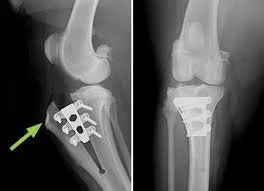

3. TTA (Tibial Tuberosity Advancement)

This surgery advances the tibial tuberosity to change the angle of the patellar ligament, stabilizing the knee.